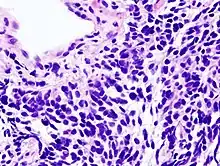

Cancer du poumon à petites cellules

Le carcinome du poumon à petites cellules (aussi appelé small cell carcinoma) est moins courant. Il a tendance à survenir dans les voies aériennes les plus grandes (bronches primaires et secondaires), et grossit vite, pour devenir assez grand[140].

La « cellule avoine » contient des granules neurosécréteurs denses (vésicules contenant des neurohormones) qui donnent une association de syndromes endocriniens et paranéoplasiques[141].

Bien que plus sensible au début à la chimiothérapie, il entraîne cependant un pronostic plus défavorable, et en est souvent au stade des métastases à la détection. Les cancers du poumon à petites cellules sont divisés en maladie à un stade limité ou à un stade extensif. Ce type de cancer est fortement associé au tabagisme[142].